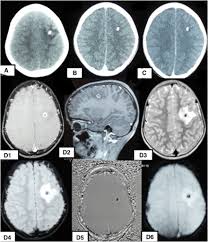

An Ambispective Cohort Study To Assess Seizure Recurrences In Children With Calcified Parenchymal Neurocysticercosis In The American Journal Of Tropical Medicine And Hygiene Volume 101 Issue 4 2019

Calcified Neurocysticercosis Lesions Trigger Symptomatic Inflammation During Antiparasitic Therapy American Journal Of Neuroradiology